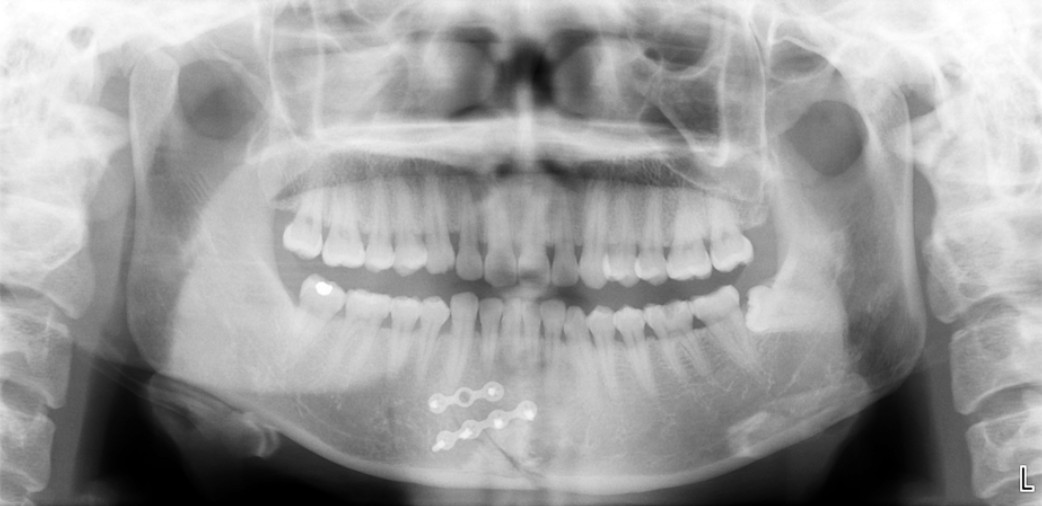

Fractura en línea media mandibular por impacto mandibular deportivo, que ha sido exitosamente reducida de forma quirúrgica por el equipo de Cirugía Maxilofacial de Clínica Kranion